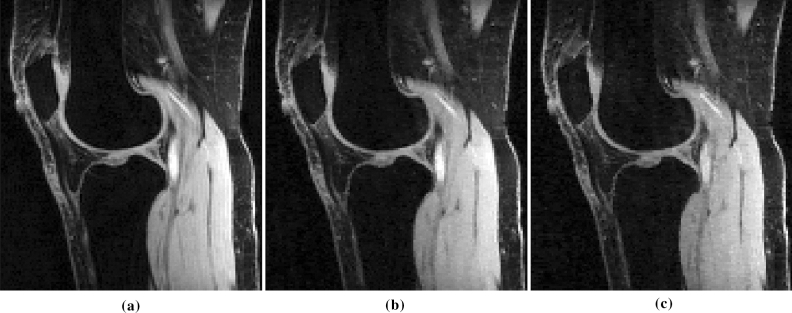

In Fig. 8, visual results with the -knee dataset illustrate the improvement due to using an optimized SP as compared to using combined variable density and Poisson disk SP, for both CS-LR and CS-DIC. We also see that the optimized SPs are different for the two reconstruction methods. Note that both optimized k-t-space SPs have a different sampling density over time (first, middle, and last time frames are shown), being more densely sampled at the beginning of the relaxation process. The auto-calibration region is in the first frame.

Figure 8.

Three frames for different relaxation times of the knee dataset, when was used, reconstructed with CS-DIC (b) and (e) and with CS-LR (h) and (k): compare these with the corresponding fully sampled (FS) measurements in (j), where the corresponding magnitude of the errors are in (c,f,i,l). Combined variable density and Poisson disk SP (d) and BASS optimized SPs for CS-DIC (a) and CS-LR (g) are also shown. Central auto-calibration area is highlighted in yellow.